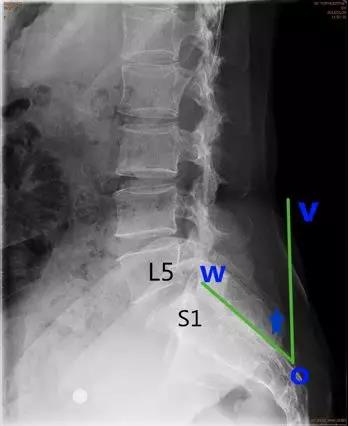

脊柱滑脱参数

- 腰骶角(lumbosacral angle):

- 腰椎纵轴和骶椎纵轴之间的夹角;

- S1上缘连线与水平线的交角。正常值为41.1°±7.7°or34°(亦称骶骨水平角)。

临床意义:增大提示有滑脱进展风险。成人若>45°则可称水平骶椎,腰骶角增大时腰椎前凸加深和骨盆前倾,导致骶髂关节劳损,腰脊柱力平衡失调,并继发腰、胸、颈段劳损称之为“水平骶椎综合症”。

- 滑脱角:S1后缘垂线与L5下终板平行线之间的夹角。正常<10°。

临床意义:>10°提示滑脱进展的风险。

- 骶骨倾(斜)角:即S1后方骶骨后缘平行线与地面垂线之间的夹角。正常值<30°。

临床意义:>30°提示滑脱进展的风险。